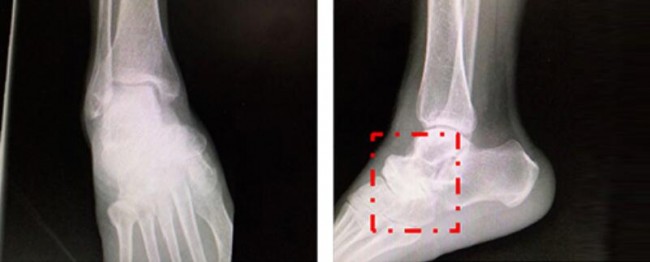

The First People’s Hospital of Huaiji County, Zhaoqing City, Guangdong Province, recently received a 55-year-old patient with a 10-year history of sprained right foot, Ms. Huang. The recurring symptoms of right foot back pain and limited walking function have brought obvious inconvenience to Ms. Huang’s health and daily life.

Traditional imaging examinations such as X-ray, CT, MR were performed by Huaiji County People’s Hospital, and the preliminary diagnosis was: 1. Osteonecrosis of the right scaphoid. 2. Osteoarthritis of the right talar navicular joint. 3. Osteoarthritis of the right heel cuboid joint. The right talus navicular joint and calcanecubic joint fusion are planned.

Professor Ding Huanwen’s team combined the patient’s symptoms and signs to clinically diagnose Muller-Weiss disease. Confirm that the patient’s diseased part is attached to the transverse joint through 3D precise positioning. Through consultation and discussion, it was decided to carry out the operation of “medial foot column extension, talus navicular joint fusion, and talar cuboid bone fusion fixation” for the patient.